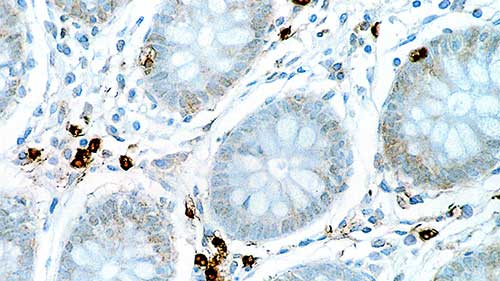

IL-6 is a multifunctional cytokine that is secreted by both lymphoid and non-lymphoid cells. It plays a key role in immune responses, hematopoiesis and is an important cytokine in cell proliferation and differentiation. It may also play an important role as an autocrine growth factor in metastatic prostate cancer. IL-6 has been reported to play a role in secretion or release of pituitary hormone in pituitary hormone secreting cells and adenomas. In addition, IL-6 has been suggested to have a trophic effect in nerve cells and to have a direct pathogenic role in CNS disorders. There are an increasing number of reports that cytokines of the IL-6 family play an important regulatory role in heart physiology.